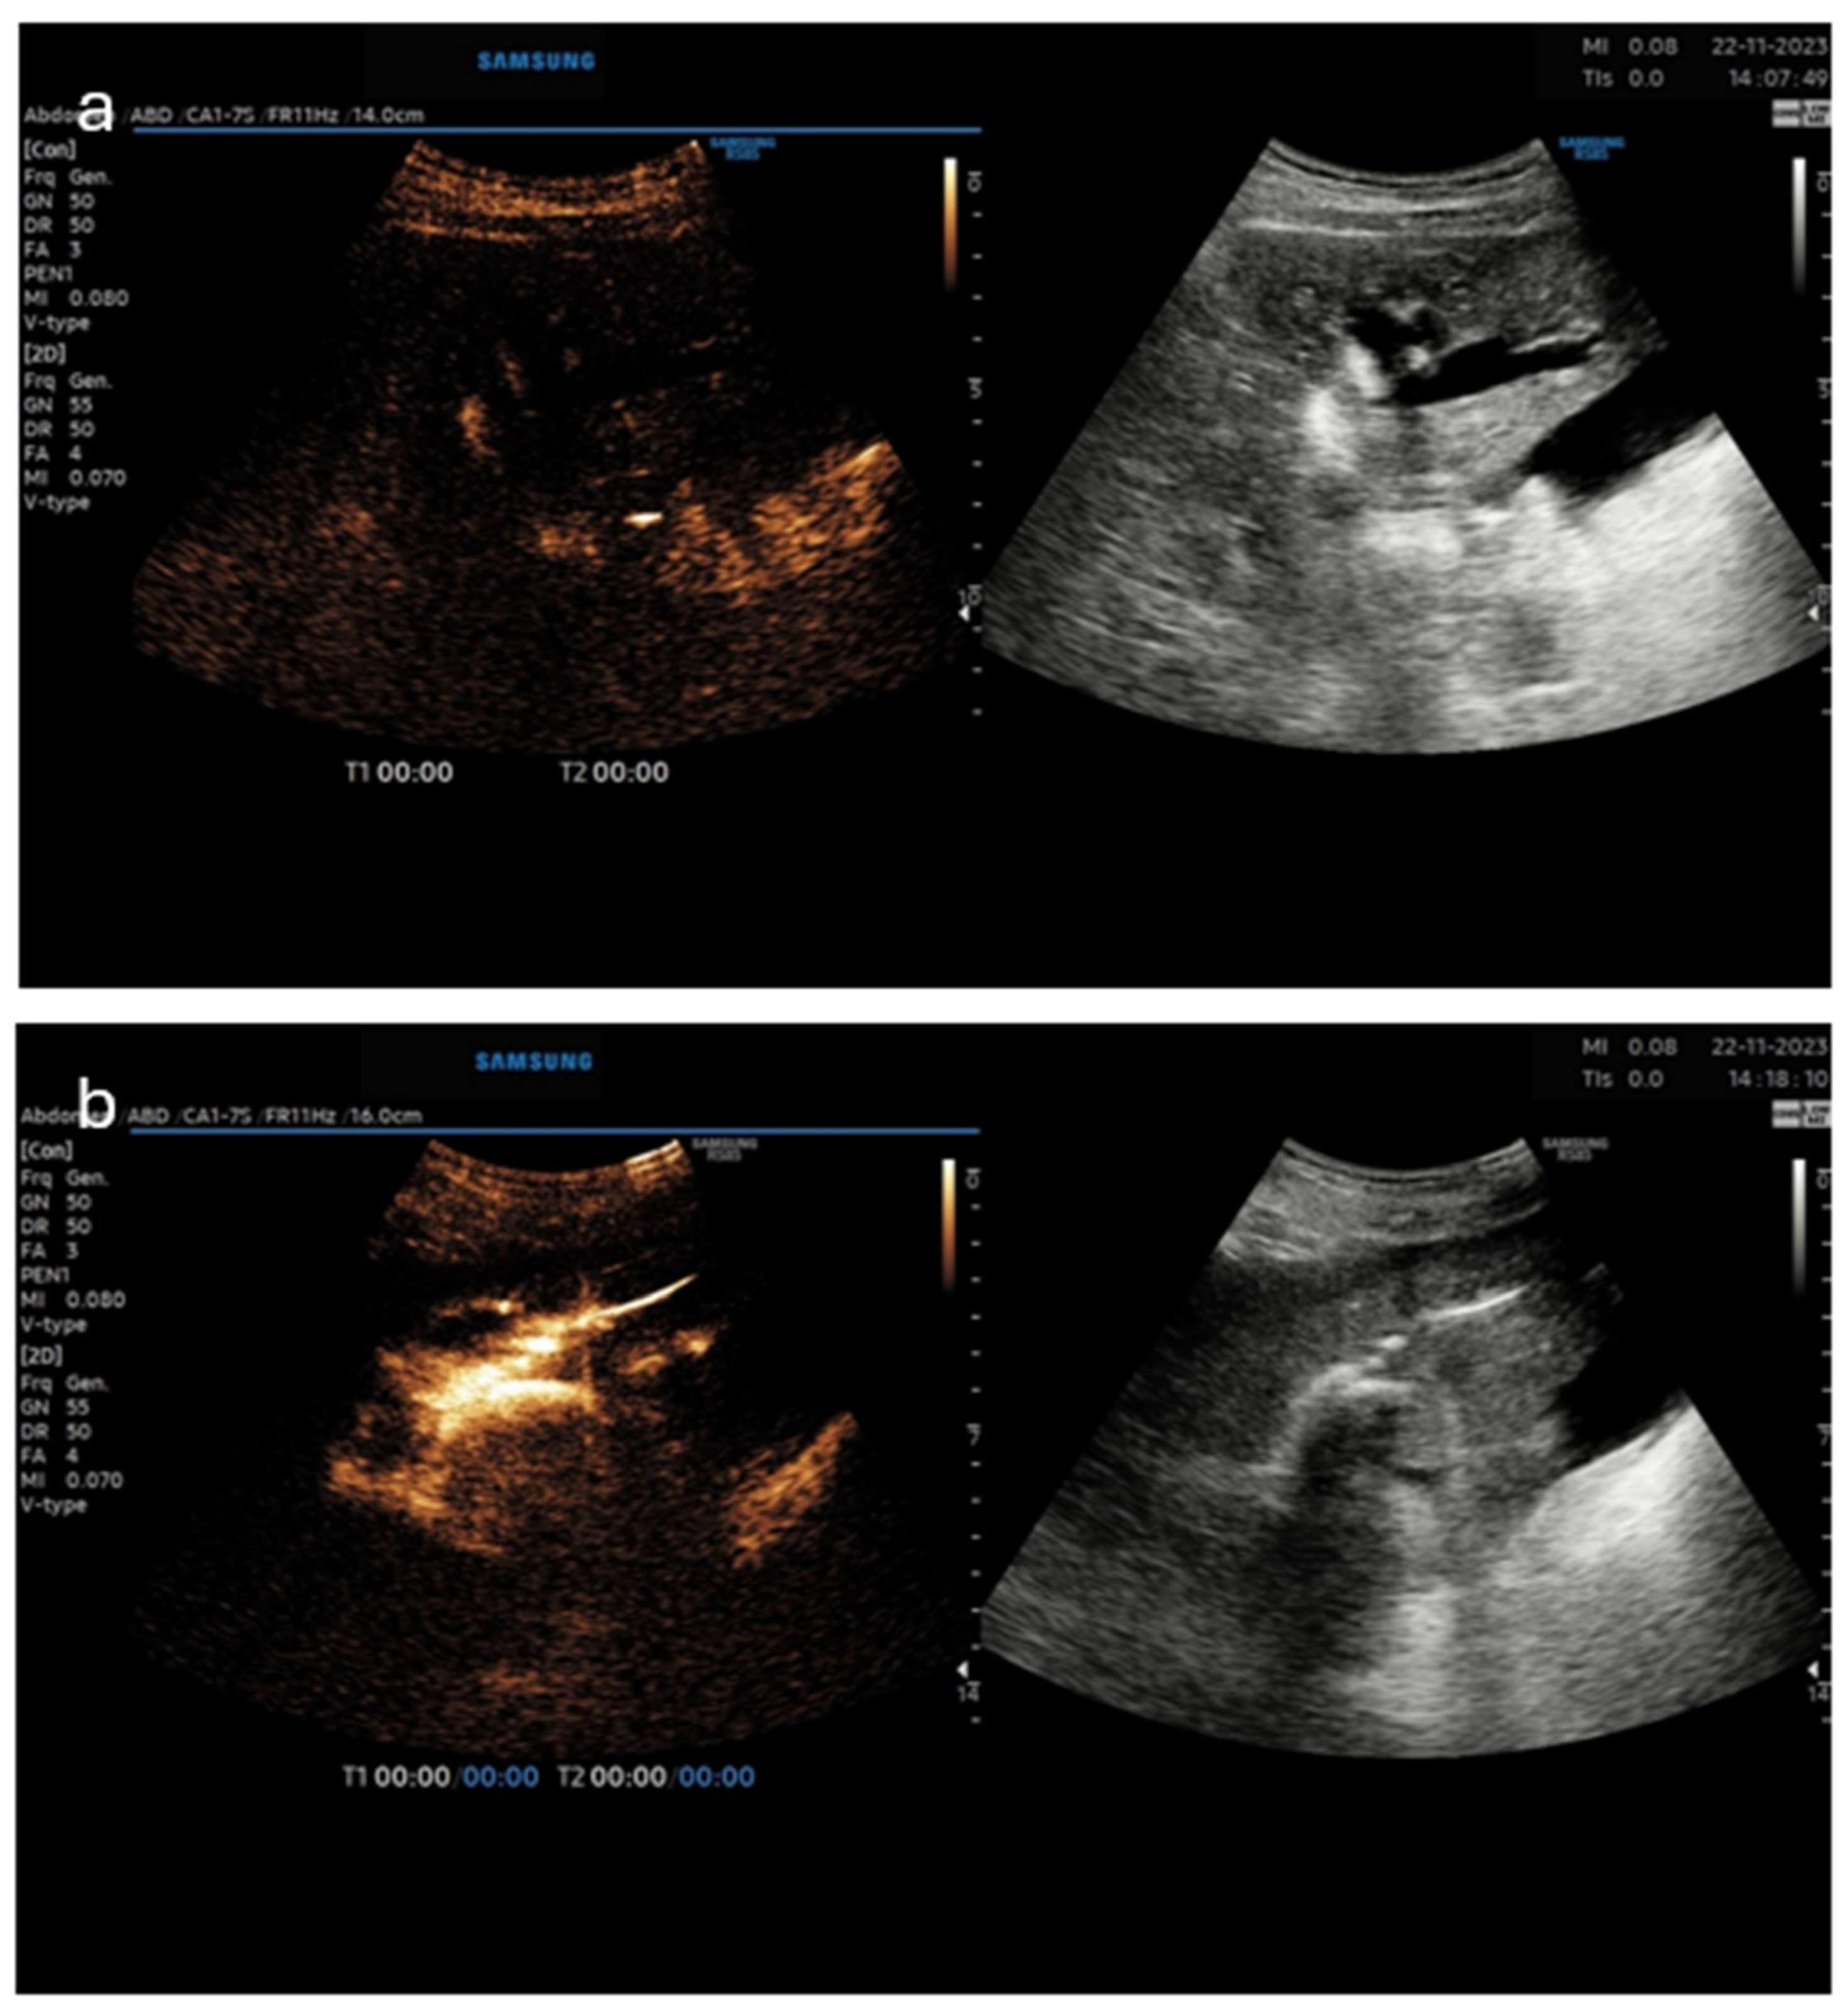

5. Pictorial Examples